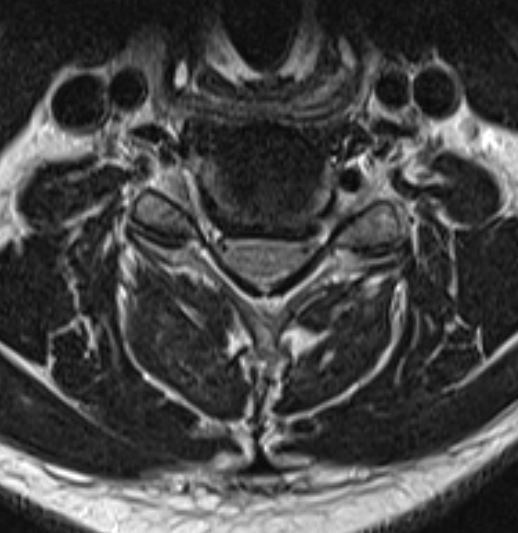

Cervical Disc Replacement. Motion sparing cervical surgery through a microscopic minimally invasive approach. By replacing the disc instead of fusing it, we allow the segment to maintain motion and restore natural alignment, decreasing the risk of breakdown in the adjacent levels while still fully decompressing the spinal cord and nerve roots. Patients maintain full neck motion without the need for a collar and are back to full activities faster. This 42 year old mechanic has been dealing with severe radiculopathy for over 2 years with no relief with conservative management. His patient reported pre-op neck disability index score was 51% (which shows he reported his symptoms were severely limiting his quality of life). His post-op neck disability index score after 2 weeks is now 8% (which implies he is no longer limited by these symptoms). He is now already back to work, without pain, with full range of motion. Posted with patient permission.